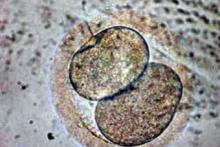

Izolace kmenových buněk z tukové tkáně (adipose-derived stem cells, ASCs), které mohou dát vznik buňkám chrupavky, skutečně možná je a je dobře zvládnutá. Velmi ale pochybuji, že by prostá injekce těchto kmenových buněk do kloubu dala vznik nové chrupavce. Proces přeměny kmenových buněk na buňky chrupavky v laboratorních podmínkách možný je, ale neprobíhá jen tak sám od sebe, ale vyžaduje manipulaci těchto kmenových buněk definovanou směsí růstových (např. TGFbeta, IGF, FGF, EGF) a transkripčních faktorů (např. Sox9).